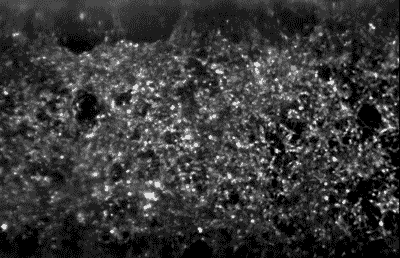

Hundreds of spinal motor neurons spontaneously communicate through electrical signals inside an Organ-Chip. Neurons fire individually (flashing dots) and in synchronized bursts (bright waves). (Cedars-Sinai)